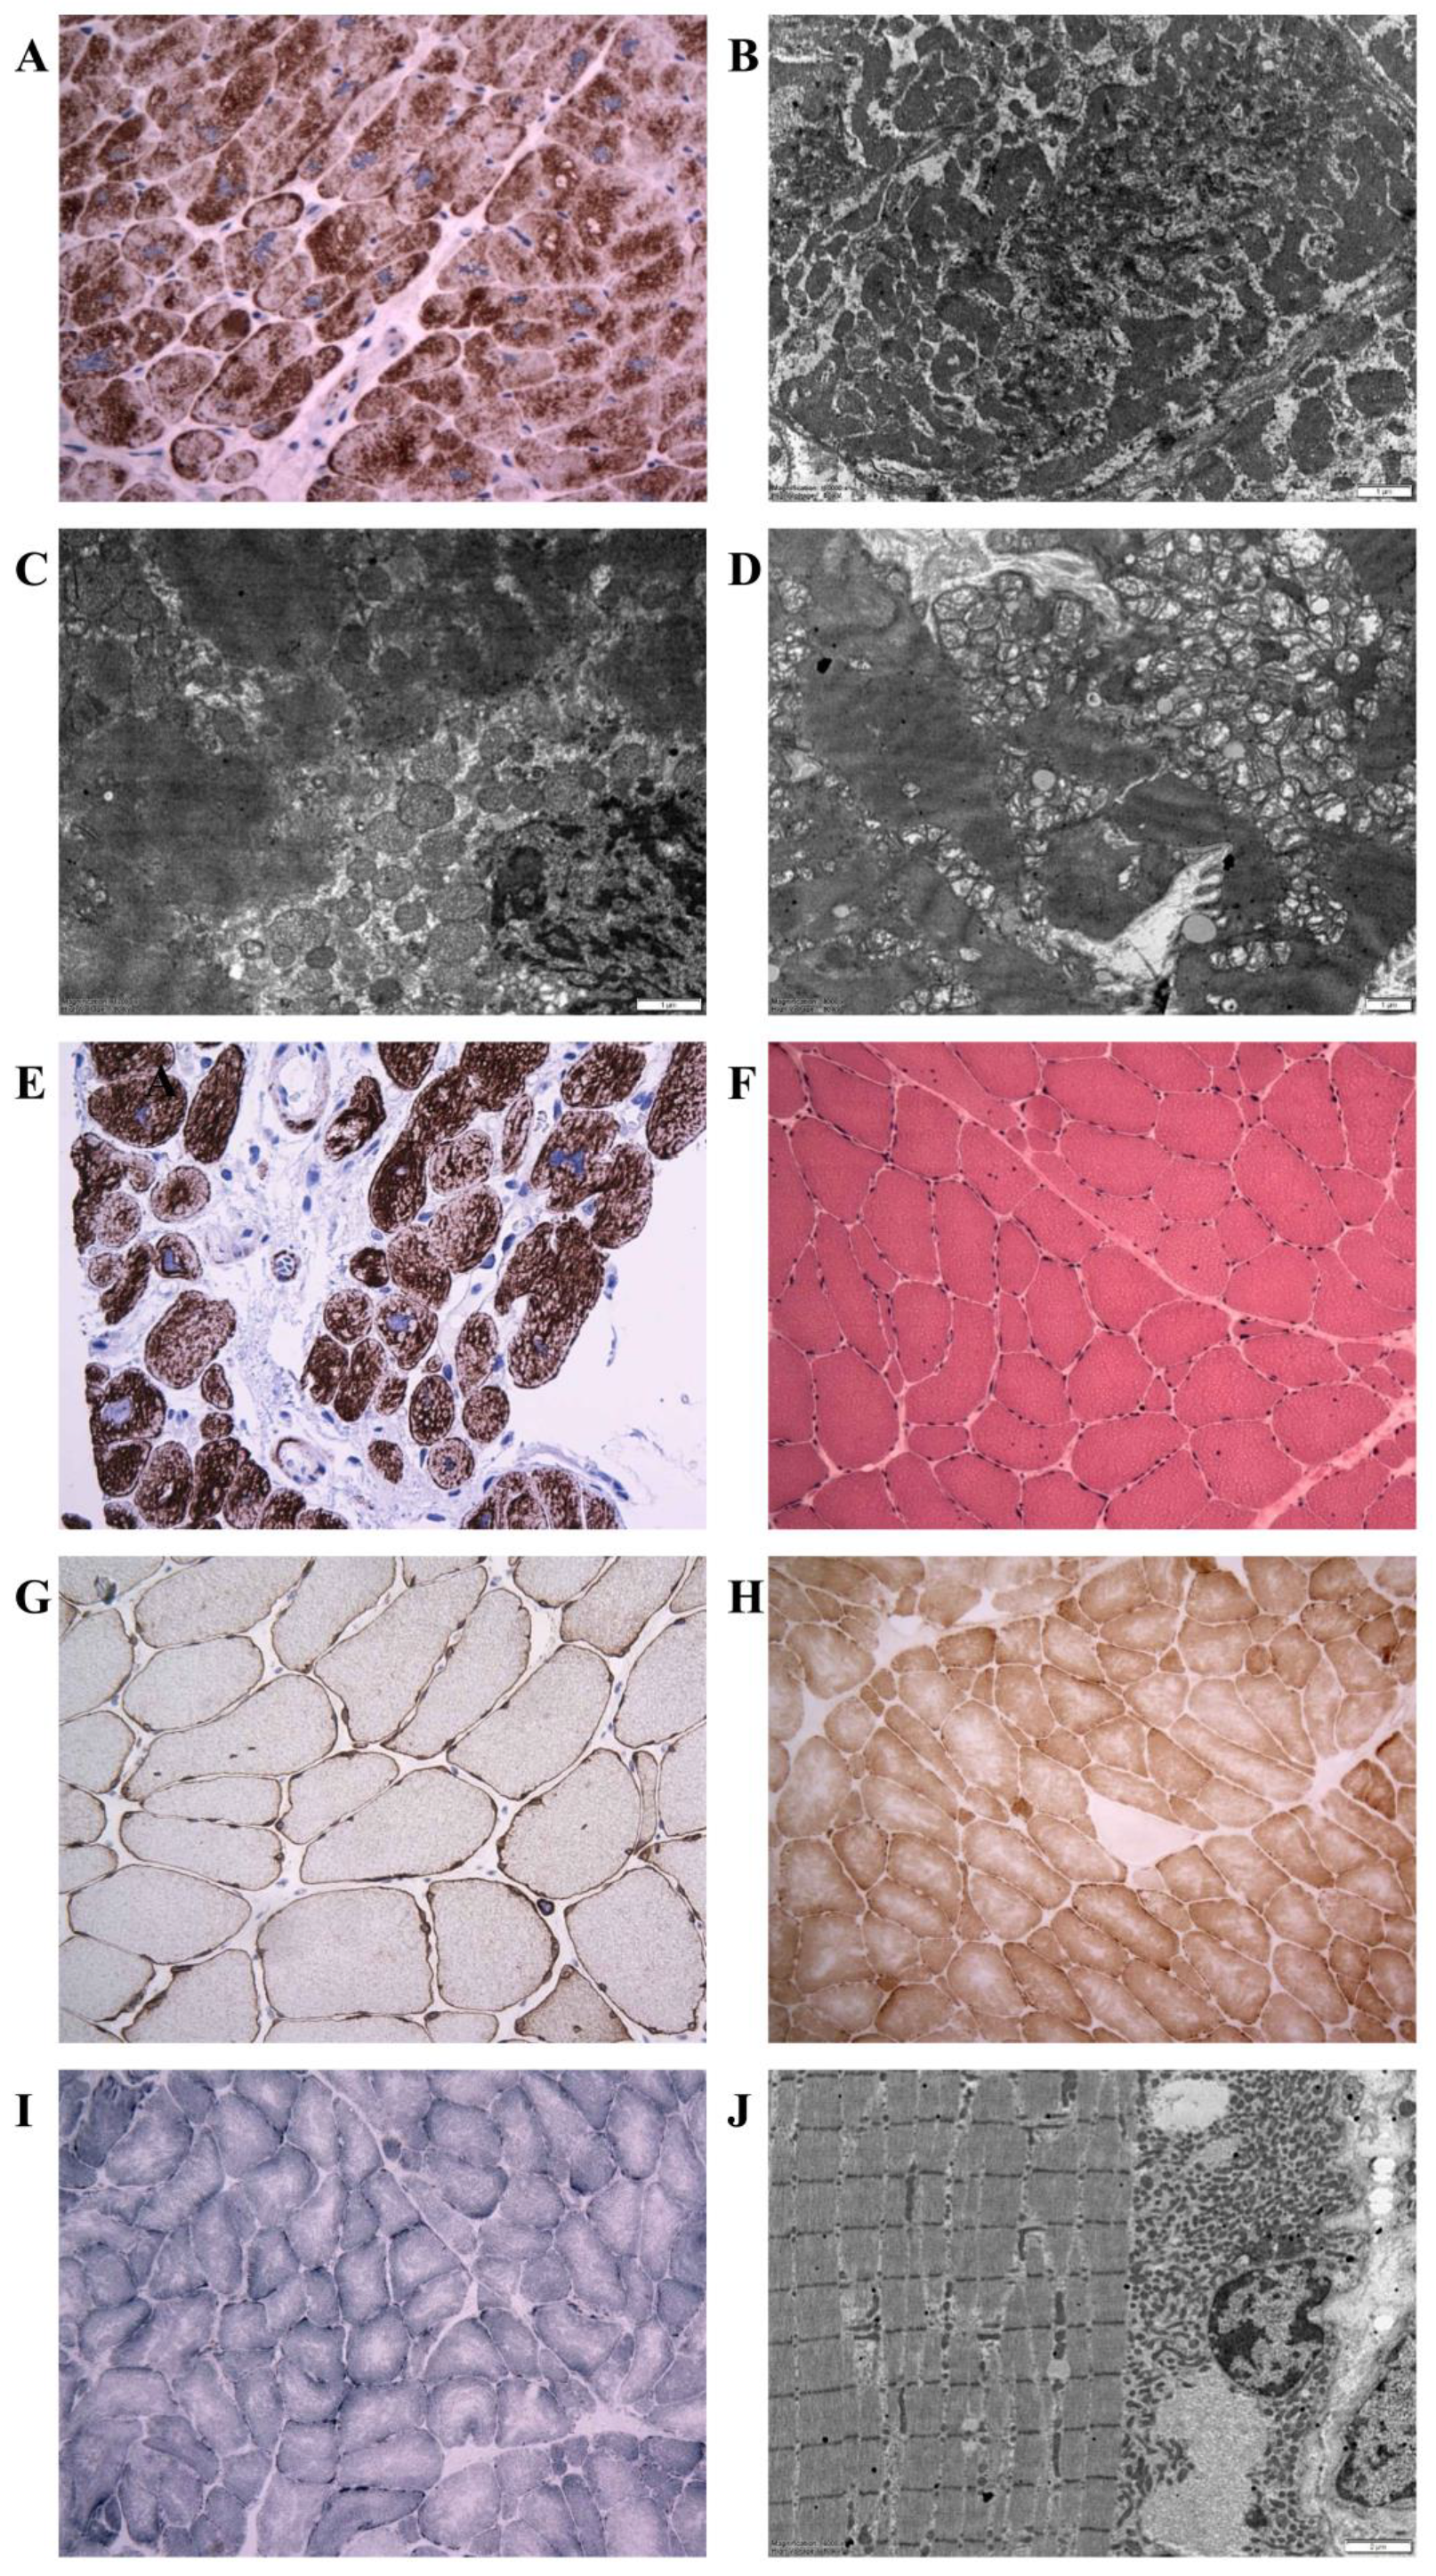

3.3. Morphology of Desminopathy in Myocardial and Skeletal Muscle Samples

3.5. Mitochondrial Function and Content in Skeletal Muscle and Heart